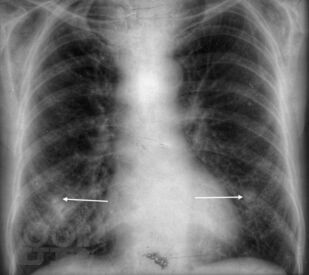

Рентгеноанатомия органов грудной клетки

Губик Е. А. Рентгеноанатомия органов грудной клетки : Учебное пособие / Е. А. Губик, Т. В. Кузина. - Чита : Издательство ЧГМА, 2023. - 76 c. - Текст : электронный // ЭБС "Букап" : [сайт]. - URL : https://www.books-up.ru/ru/book/rentgenoanatomiya-organov-grudnoj-kletki-16748814/ (дата обращения: 26.05.2026). - Режим доступа : по подписке.

В данном электронном пособии систематизированы и подробно изложены сведения о рентгеновской анатомии органов грудной клетки.